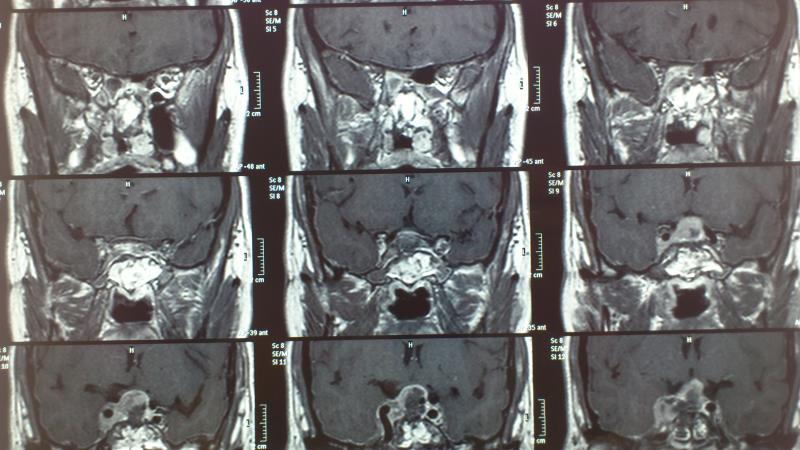

Προεγχειρητικός απεικονιστικός έλεγχος